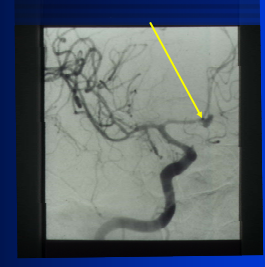

Fibromuscular Dysplasia: hyperplasia of smooth muscle and fibrous tissue alternating with thin, fibrotic regions; at risk for developing occlusions, dissection, aneurysm